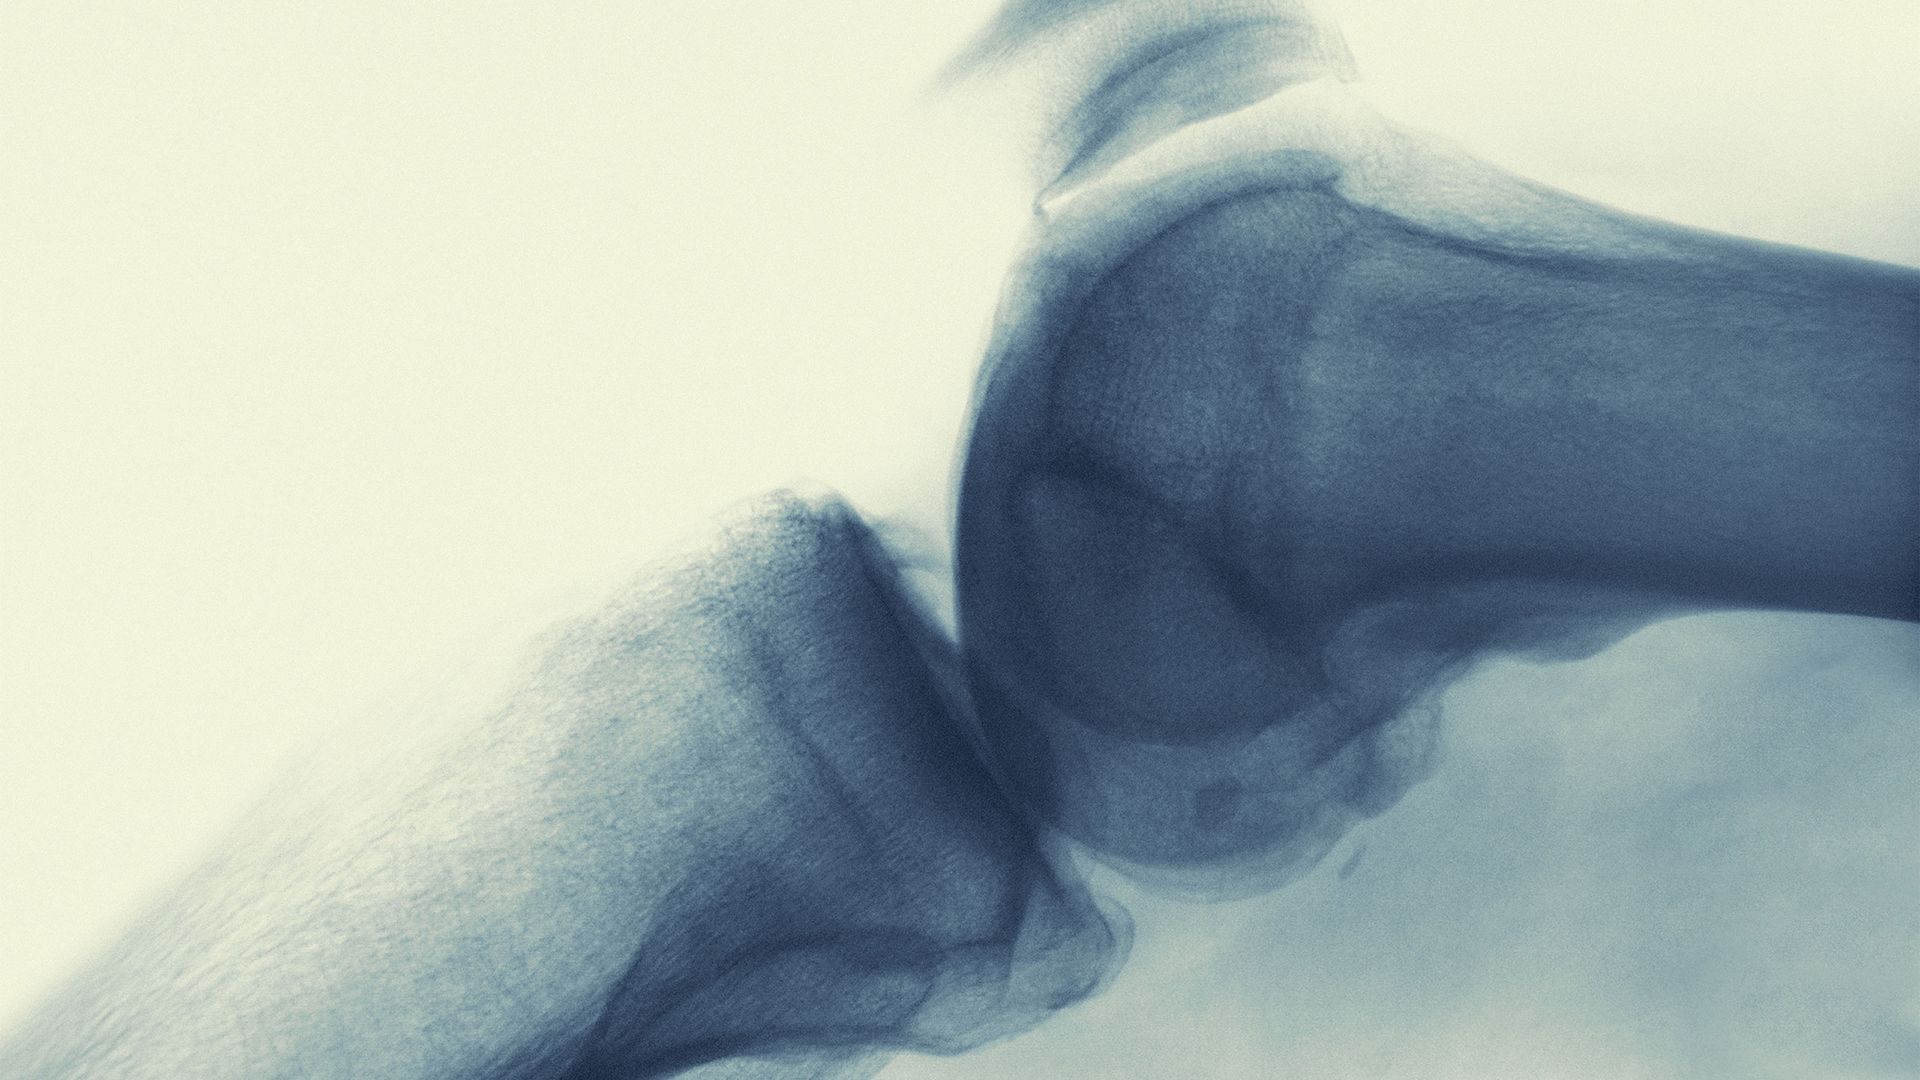

Tenosynovial giant cell tumors (TGCTs) refer to rare types of tumors that form on the tissues that make up the joints. In the majority of cases, TGCTs are benign (non-cancerous), but they can be painful, can cause swelling and stiffness in the joints, and can lead to disability. In most cases, TGCTs are treated with surgery. Unfortunately, recurrence is common, and people who have TGCTs often require follow-up surgeries to address tumors that return.